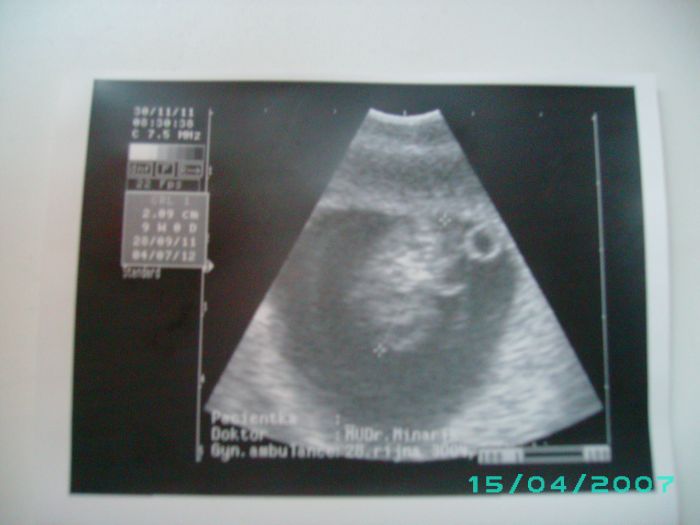

Ahojik devcatka tak jsem se vam prisla pochlubit jsem se vratila od dr a miminko je v poradku a srdicko bije jako zvon prikladam vam fotecku je hlavickou dolu.